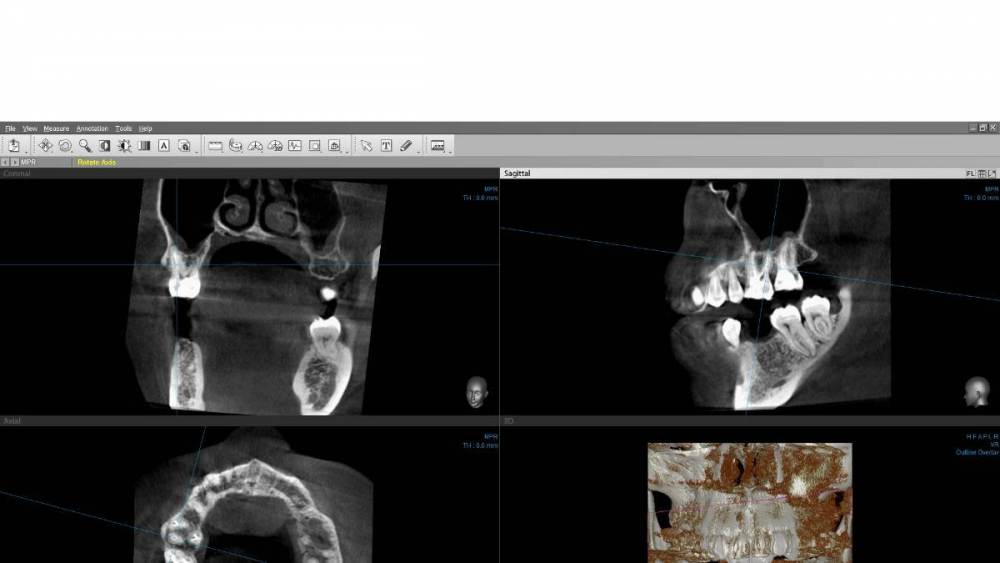

Carioznik Опубликовано 10 июля, 2023 Поделиться Опубликовано 10 июля, 2023 (изменено) образ диска с Вашим КТ - не открывается (поврежден). Либо создан с ошибкой, либо не загрузился нормально. Можно просто все папки на диске заархивировать и закачать. Хотя, думаю, уже пора новое КТ делать и разбираться на его основе. Изменено 10 июля, 2023 пользователем Carioznik Ссылка на комментарий

wladdX Опубликовано 12 июля, 2023 Поделиться Опубликовано 12 июля, 2023 Исследование от 27.12.2021. Лучше бы поновее Ссылка на комментарий

Carioznik Опубликовано 13 июля, 2023 Поделиться Опубликовано 13 июля, 2023 по этому старому КТ: на 16 - есть пропущенный канал, от этого, на одном из корней - есть небольшой воспалительный процесс (на тот момент). "Само не заживет", будет только расти, может, на сегодняшний момент - уже стал большой). Но жалобы в таких случаях обычно другие. Делайте новое КТ (по старому только гадать...) и снова, очный осмотр стоматолога, явно понадобится. 1 Ссылка на комментарий